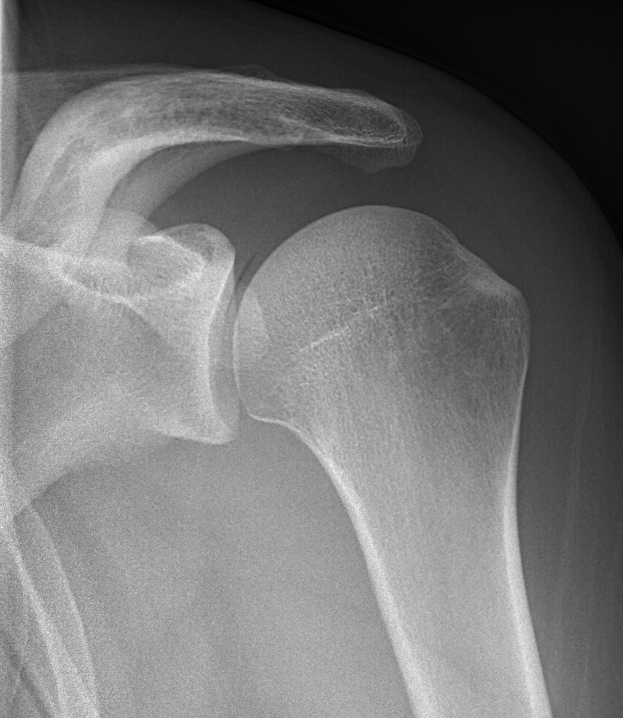

Ein Röntgenbild, das die Knochen und Bänder eines Schultergelenks zeigt.Lina Koch

Verteidiger Joel Felix von Arminia Bielefeld hat sich eine schwere Schulterverletzung zugezogen, die ihn monatelang außer Gefecht setzen wird. Der Vorfall ereignete sich während des Spiels gegen Holstein Kiel, woraufhin er frühzeitig vom Platz musste.

Felix wurde bereits nach 17 Minuten in der Partie gegen Kiel ausgewechselt. Spätere medizinische Untersuchungen bestätigten eine schwere Verletzung des Schultergelenks. In den kommenden Tagen soll er operiert werden.